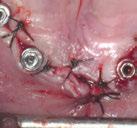

En las piezas 16 y 17 el paciente presentaba restauraciones atornilladas de metalcerámica sobre implantes oseointegrados. Se planificó realizar estas en una fase posterior a la rehabilitación de las piezas dentarias mediante flujo digital con bases de titanio y cuerpos de escaneo.

SW 5.2, Dentsply Sirona) (Figuras 22-27), la cual fue materializada en dos tipos de materiales a partir de bloques cerámicos IPS Empress CAD y cerámica vítrea de disilicato de litio IPS E.max CAD (Figuras 28-30)

Finalmente, las restauraciones se cementaron adhesivamente (Figuras 31-35). En las piezas 16 y 17 se realizaron restauraciones cementoatornilladas como última fase de tratamiento. Se recomendó al paciente una férula de protección superior la cual fue elaborada mediante un flujo de trabajo digital (Figura 36)